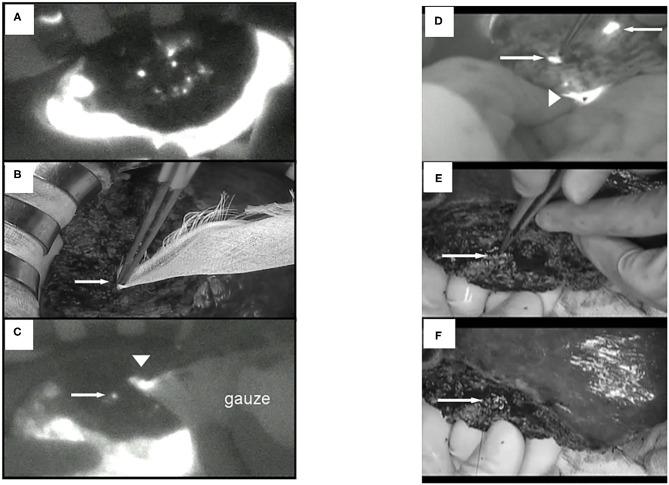

肝脏肿瘤的近红外荧光成像与光动力疗法

Surgery with fluorescence equipment has improved to treat the malignant viscera, including hepatobiliary and pancreatic neoplasms. In both open and minimally invasive surgeries, optical imaging using near-infrared (NIR) fluorescence is used to assess anatomy and function in real time. Here, we review a variety of publications related to clinical applications of NIR fluorescence imaging in liver surgery. We have developed a novel nanoparticle (indocyanine green lactosome) that is biocompatible and can be used for imaging cancer tissues and also as a drug delivery system. To date, stable particles are formed in blood and have an ~10-20 h half-life. Particles labeled with a NIR fluorescent agent have been applied to cancer tissues by the enhanced permeability and retention effect in animals. Furthermore, this article reviews recent developments in photodynamic therapy with NIR fluorescence imaging, which may contribute and accelerate the innovative treatments for liver tumors.

使用荧光设备的手术已得到改进,用于治疗包括肝胆和胰腺肿瘤在内的恶性内脏器官。在开放手术和微创手术中,使用近红外(NIR)荧光的光学成像用于实时评估解剖结构和功能。在此,我们综述了一系列与NIR荧光成像在肝脏手术中的临床应用相关的出版物。我们开发了一种新型纳米颗粒(吲哚菁绿脂质体),它具有生物相容性,可用于癌症组织成像,也可作为药物递送系统。迄今为止,稳定的颗粒在血液中形成,半衰期约为10 - 20小时。用NIR荧光剂标记的颗粒已通过动物体内的增强渗透和滞留效应应用于癌症组织。此外,本文还综述了NIR荧光成像在光动力治疗方面的最新进展,这可能有助于并加速肝脏肿瘤的创新治疗。